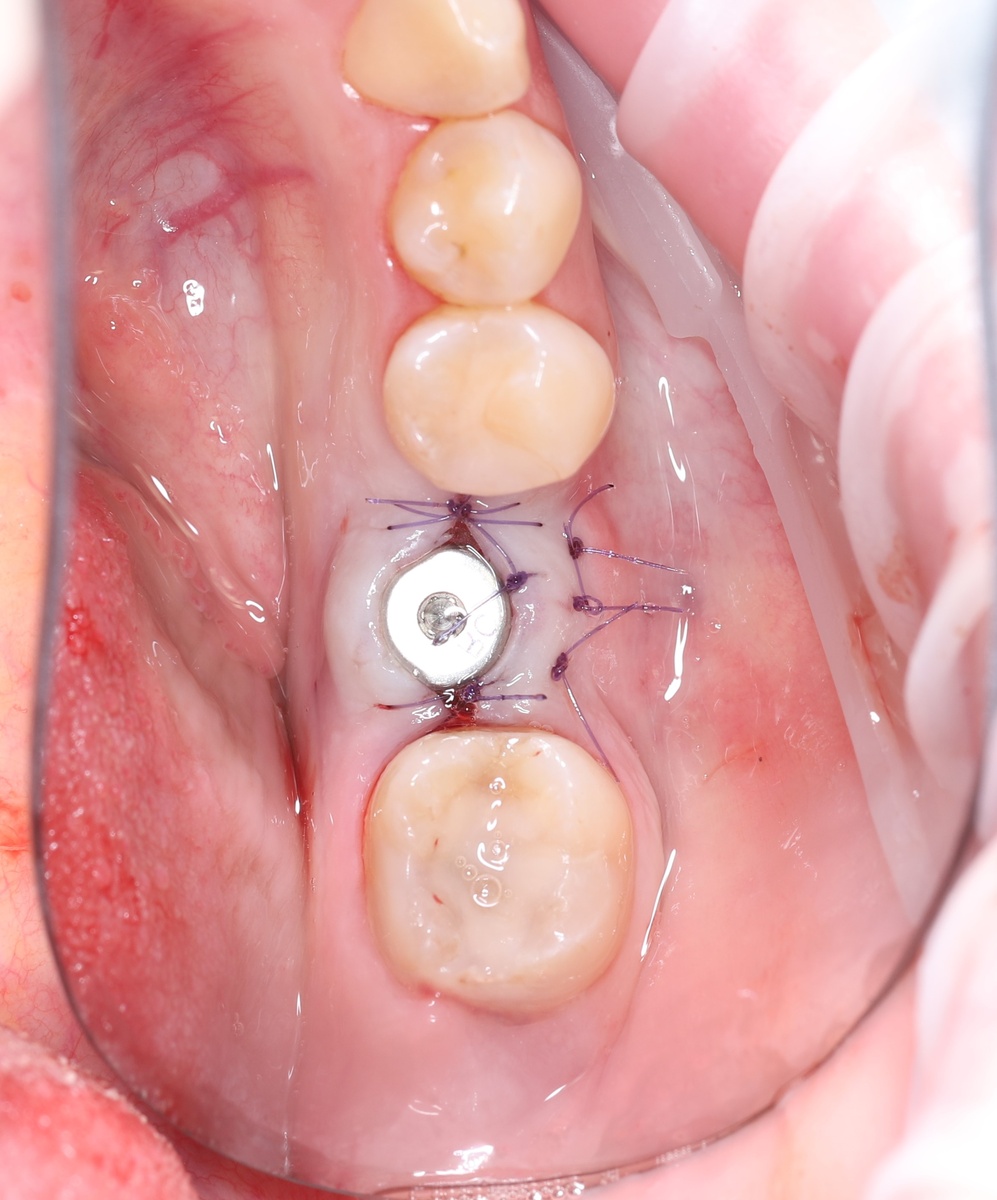

Фото сразу после установки имплантата, формирователя и десневой пластики:

-2